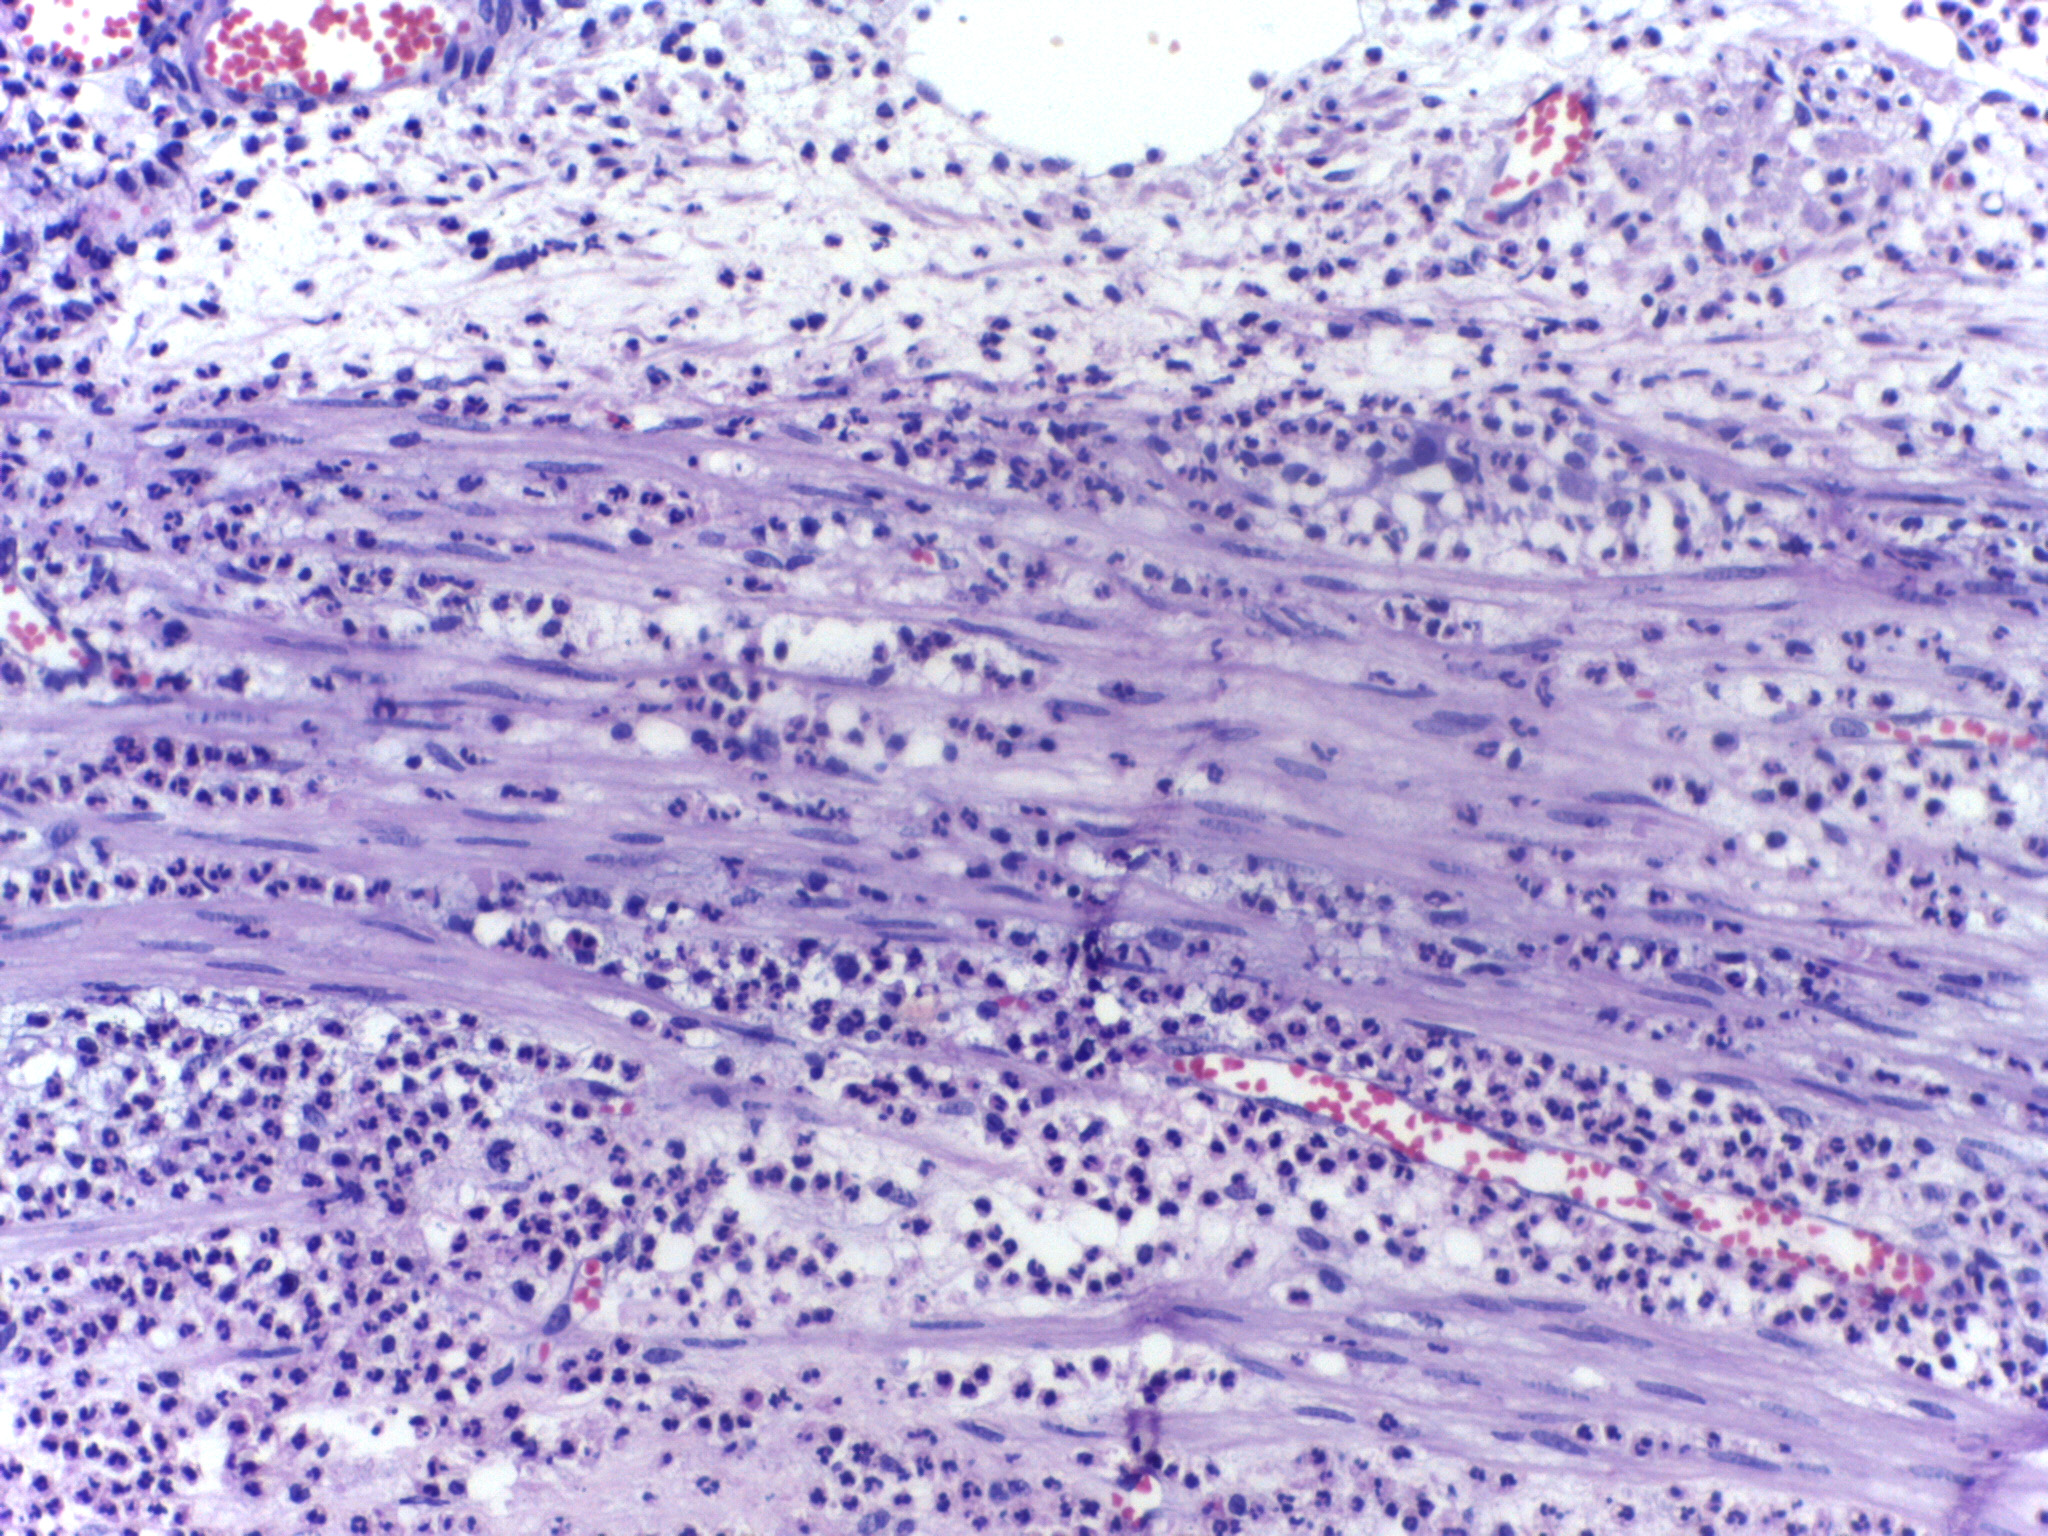

호중구는 백혈구의 한 종류로, 과립구 중 하나이다. 중성 색소에 염색되는 살균성 과립을 가지고 있으며, 활발한 아메바 운동을 통해 생체 내 침입한 세균이나 진균류를 잡아먹고(식작용) 살균하여 감염을 막는다.

골수에서 생성되어 성숙하며, 염증 반응이 일어나는 곳으로 이동하여 세균, 진균 등의 이물질을 제거하고 분해하여 생체를 방어한다.

탐식된 세균은 세포 내 소기관인 리소좀과 융합, 리소좀 내의 산소 의존 기전에 의해 살균되고 가수분해 효소에 의해 분해된다. 호중구는 성숙 단계에 따라 핵의 형태가 달라져 간상핵구와 분엽핵구로 분류할 수 있다. 혈액 내 백혈구의 절반 이상이 호중구이다.

호중성 과립구는 말초 혈액 도말 실험에서 평균 지름 12 - 15μm로 나타난다. 자동 세포계수기에서 순수한 호중구 부유액을 분석하면 평균 지름은 8 - 9μm이다.[14]림프구, 단핵구 및 기타 백혈구와 달리, 호산구, 호염기구와 함께 호중구는 엽이 있는 핵을 가진 다형핵세포에 속한다. 핵은 특징적인 엽 형태로, 염색질로 서로 연결된다. 호중구는 성숙하면서 핵 분절이 증가하여 과다분절 상태가 된다. 또한 성숙하면서 핵소체가 사라지는 소수의 유핵세포에 속한다.[104] 세포질에 있는 골지체는 작고, 미토콘드리아와 리보솜이 드물게 존재하며 조면소포체는 없다.[104] 세포질에는 200여 개의 과립이 들어 있고, 그 중 1/3은 아주르친화성 과립이다.[104]

표준 혈액 세포 염색인 김자 염색으로 중성 색소에 염색되는 특수 과립을 가지고 있으며, 성숙하면 핵이 분열(분엽)되므로 "다형 핵 백혈구"라고 불리기도 한다. 최종 완성형인 호중구는 "'''분엽 핵구'''"라고 불리며, 핵은 분열되지만 핵 사이는 핵사로 연결되어 있다. 분엽 핵구가 되기 전에는 핵이 크게 굽어진 젤리빈 모양의 막대 모양인 단계가 있는데 이를 '''간상 핵구'''라고 한다. 호중성 과립은 리소좀의 일종이며, 골지체에서 만들어진다. 직경은 12~15μm[77]이며, 백혈구 중에서는 림프구보다 크고, 단구·대식세포보다 작다.[78]